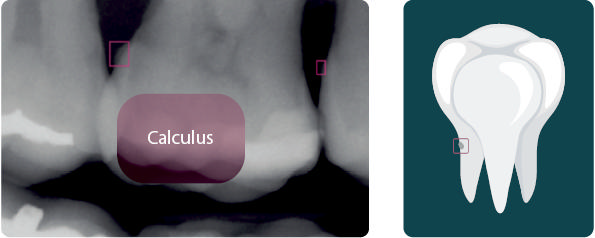

Tandsten

• Kvantificerer og lokaliserer tandsten

• Relevant for både TL og TP

• God bro mellem diagnostik og profylakse